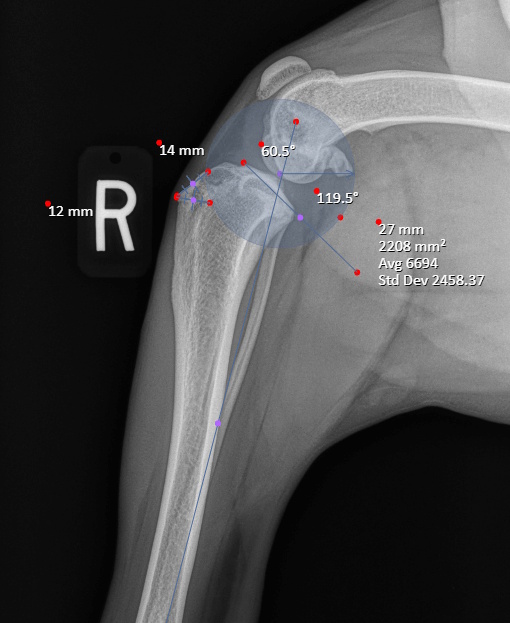

Hip Dysplasia in canines

Surgical Treatments of Hip Dysplasia